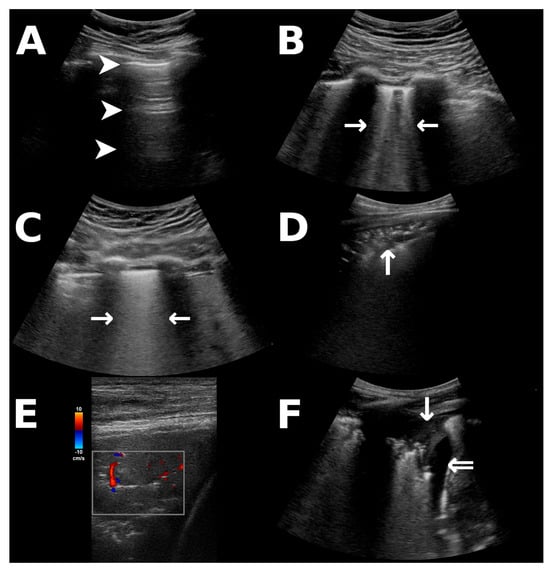

During the ongoing pandemic of coronavirus disease-19 (COVID-19), lung ultrasound (LUS) has emerged as a powerful diagnostic tool in detecting the pulmonary involvement of infection [1]. LUS provides bedside imaging without radiation exposure and can be repeated perpetually while providing a higher sensitivity than bedside radiography, particularly in COVID-19 [1,2]. Interstitial involvement in lung disease is indicated by B-lines on LUS [3,4], which are distinguishable in moderate pathologies (Figure 1B) and may form indistinguishable, coalescent B-lines (Figure 1C) when interstitial involvement progresses to alveolar edema, corresponding to “white lung” in conventional imaging [4]. B-lines may occur in infectious disease, pulmonary edema, and other interstitial lung diseases [3,4]. Furthermore, consolidations that reach the pleura and pleural effusion (Figure 1D–F) are detectable via LUS [1,3]. Critically ill patients are at a high risk of suffering from complications during in-hospital transport to acquire radiological imaging [5], whereas LUS can be performed at the patients’ bedside. Many pulmonary complications in the intensive care unit (ICU) unrelated to COVID-19, for instance, the development of a pneumothorax, are also reliably detected via LUS [4].

Figure 1.

Ultrasonographic findings that were incorporated into the scoring system. All images were obtained from patients in our study population. (A) A-lines as reverberations of the pleural line (arrowheads) indicate fully aerated lungs or pneumothorax, distinguishable by dynamic pleural gliding [3,4]. (B,C) B-lines (horizontal arrows) arising from the pleural line indicate interstitial pathology and appear distinct (B) or merge to form coalescent B-lines (C), the latter corresponding to alveolar edema [4]. (D) Peripheral consolidations (vertical arrow) appear tissue-like and may contain hyperechoic air bronchograms. (E) Color Doppler ultrasonography of a pulmonary consolidation (red: flow towards the ultrasound probe, blue: flow away from the probe; scale for reference) in COVID-19 may demonstrate diminished pulmonary perfusion [1]. (F) Atelectatic lung (vertical arrow) within a pleural effusion (double arrow).